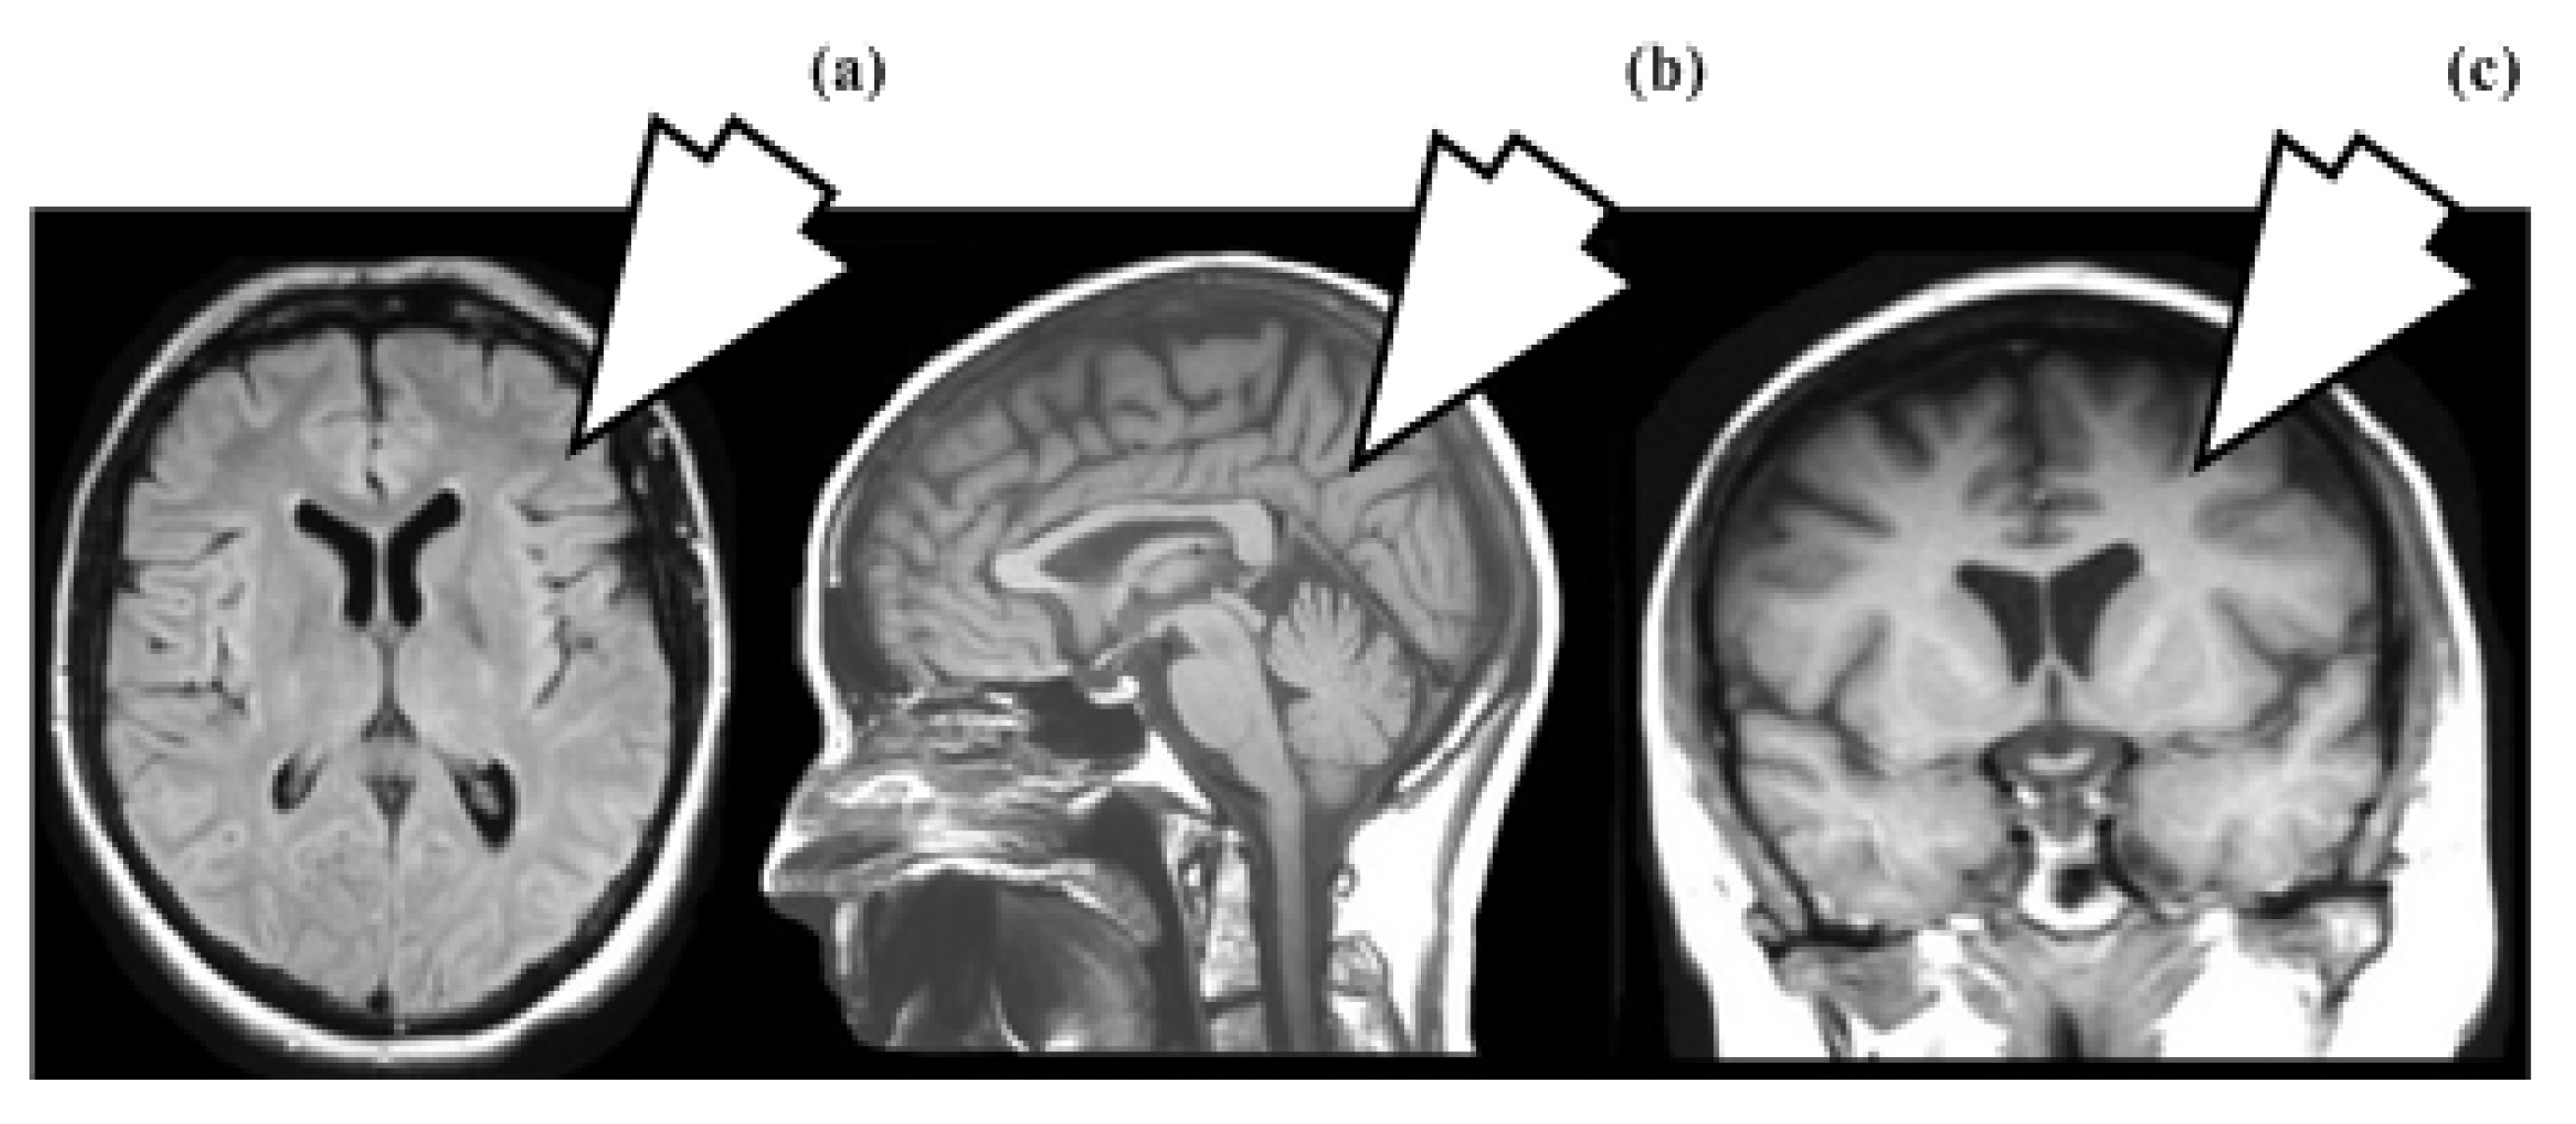

2.3. Clinical Relevance of MRI Sequence

4.2. Clinical Applications of Magnetic Resonance Imaging